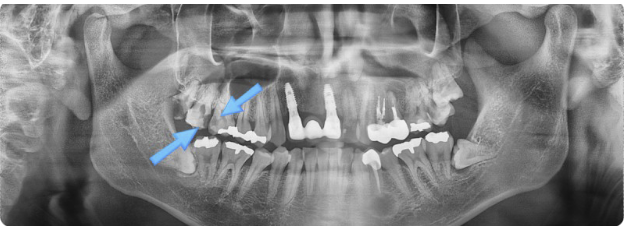

검사 결과, 충치가 이전보다 훨씬 크게 진행된 모습을 확인할 수 있었습니다.

이 사례에서는, 가장 뒤쪽에 부러진 사랑니는 발치를 진행하였고, 앞쪽 화살표로 표시된 두 개 치아는 신경치료를 시행하게 되었습니다.

충치 제거 후, 치아 신경이 위치한 통로인 치수강을 개방하여 내부 상태를 확인했습니다.

검사 결과, 오른쪽 치아의 치수강은 비교적 깨끗했지만, 왼쪽 치아는 내부 오염이 심한 상태였습니다.

치수강 오염이 심한 경우, 충치가 치아 뿌리 깊숙이까지 퍼졌을 가능성이 높아집니다. 이러한 상황에서는 치료를 성공적으로 진행하더라도 치아의 수명이 길지 않은 경우가 많습니다.